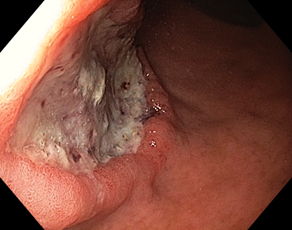

Эндоскопическая классификация стадий течения язвенного процесса по Sakita-Miwa

|

A1 |

H1

S1

A2

H2 |

S2 |

Рисунок 1. Стадии регрессии (заживления) язвы желудка и их характерные черты:

A (Active). Активная стадия (обострение)

A1. Слизистая оболочка, окружающая язву, выглядит набухшей в результате отёка, регенерация эпителия отсутствует.

A2. Отёк слизистой оболочки вокруг язвы уменьшился, край язвы отчётливо виден и в крае язвы появились первые ростки регенерирующего эпителия. По периметру язвы часто прослеживается красный ободок, а непосредственно по краю – циркулярный белый струп. Обычно, сходящиеся складки слизистой оболочки прослеживаются вплоть до края язвы.

H (Healing). Стадия заживления

H1. Слой белого фибрина, покрывающий язву, становится тонким, а регенерирующий эпителий распространяется непосредственно на основание язвы. Градиент между краем и дном язвы сглаживается. Но кратер язвы все еще очевиден, и край язвы отчётливо виден. Диаметр язвенного дефекта составляет примерно от половины до двух третей диаметра язвы в стадии A1.

H2. Язвенный дефект меньше, чем в стадии H1, и регенерирующий эпителий покрывает большую часть дна язвы. Площадь слоя белого фибрина составляет примерно от четверти до трети площади язвы в стадии А1.

S (Scarring). Стадия рубца

S1. Регенерирующий эпителий полностью покрывает дно язвы. Белый слой фибрина полностью исчез. Первоначально зона регенерации выглядит ярко красной. При прицельном осмотре можно увидеть большое количество капилляров. Сформировался "красный рубец".

S2. В срок от нескольких месяцев до нескольких лет исходно красный рубец принимает цвет окружающей слизистой оболочки. Сформировался «белый рубец».

Комментарий. Плановое эндоскопическое исследование подтверждает наличие язвенного дефекта, уточняет его локализацию, форму, размеры, глубину, состояние дна и краев язвы, позволяет выявить признаки пенетрации, рубцовой деформации и стенозирования просвета органа. Плановое эндоскопическое исследование дает возможность обнаружить другие сопутствующие изменения слизистой оболочки и определить нарушения гастродуоденальной моторики. Для оценки стадии язвенного процесса (обострение, заживление, рубцевание) целесообразно использовать общепринятую в мире классификацию Sakita-Miwa (рис.1).